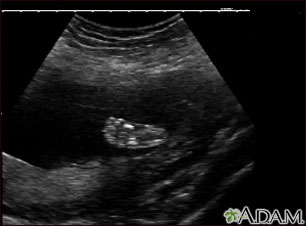

This is a normal ultrasound of a fetus at 19 weeks gestation. The right foot, including the developing bones, are clearly visible in the middle of the screen.